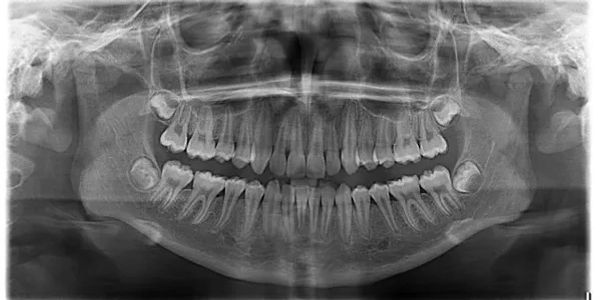

"At our dental clinic in Ghaziabad, we offer the convenience of OPG X-rays, a comprehensive imaging solution that provides a panoramic view of your oral health. Benefit from precise diagnostics and thorough assessments, ensuring comprehensive care tailored to your individual dental needs."